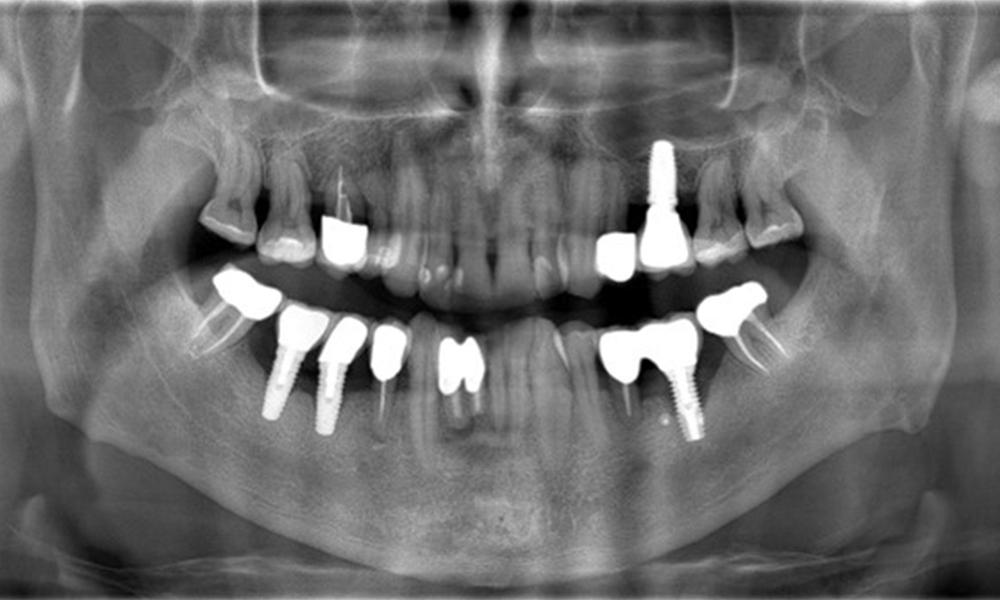

The X-ray images show the progression of bone loss.

The X-ray images show the progression of bone loss in the area of the implant in region 36: dental film from 11.02.2021 (left) and dental film from 18.01.2024 (right).

OPG: 26/02/2024 Dental X-ray: 18/01/2024